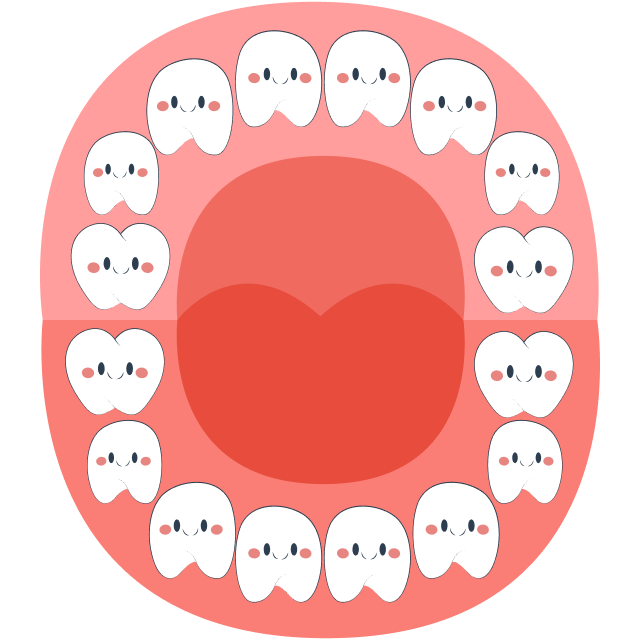

At around 6 years old, children prepare to lose their first tooth, and primary (baby) teeth will gradually be replaced by permanent teeth. The tooth replacement sequence typically begins with the eruption of the first molar (tooth number 6) and ends with the eruption of tooth number 7 around the age of 12.

During this stage, parents should closely monitor their child’s tooth replacement process and schedule regular dental check-ups. This helps detect common abnormalities early, such as missing tooth buds, extra teeth in the midline gap, or impacted teeth (mesiodens), which can obstruct tooth eruption and affect the positioning of the remaining teeth.